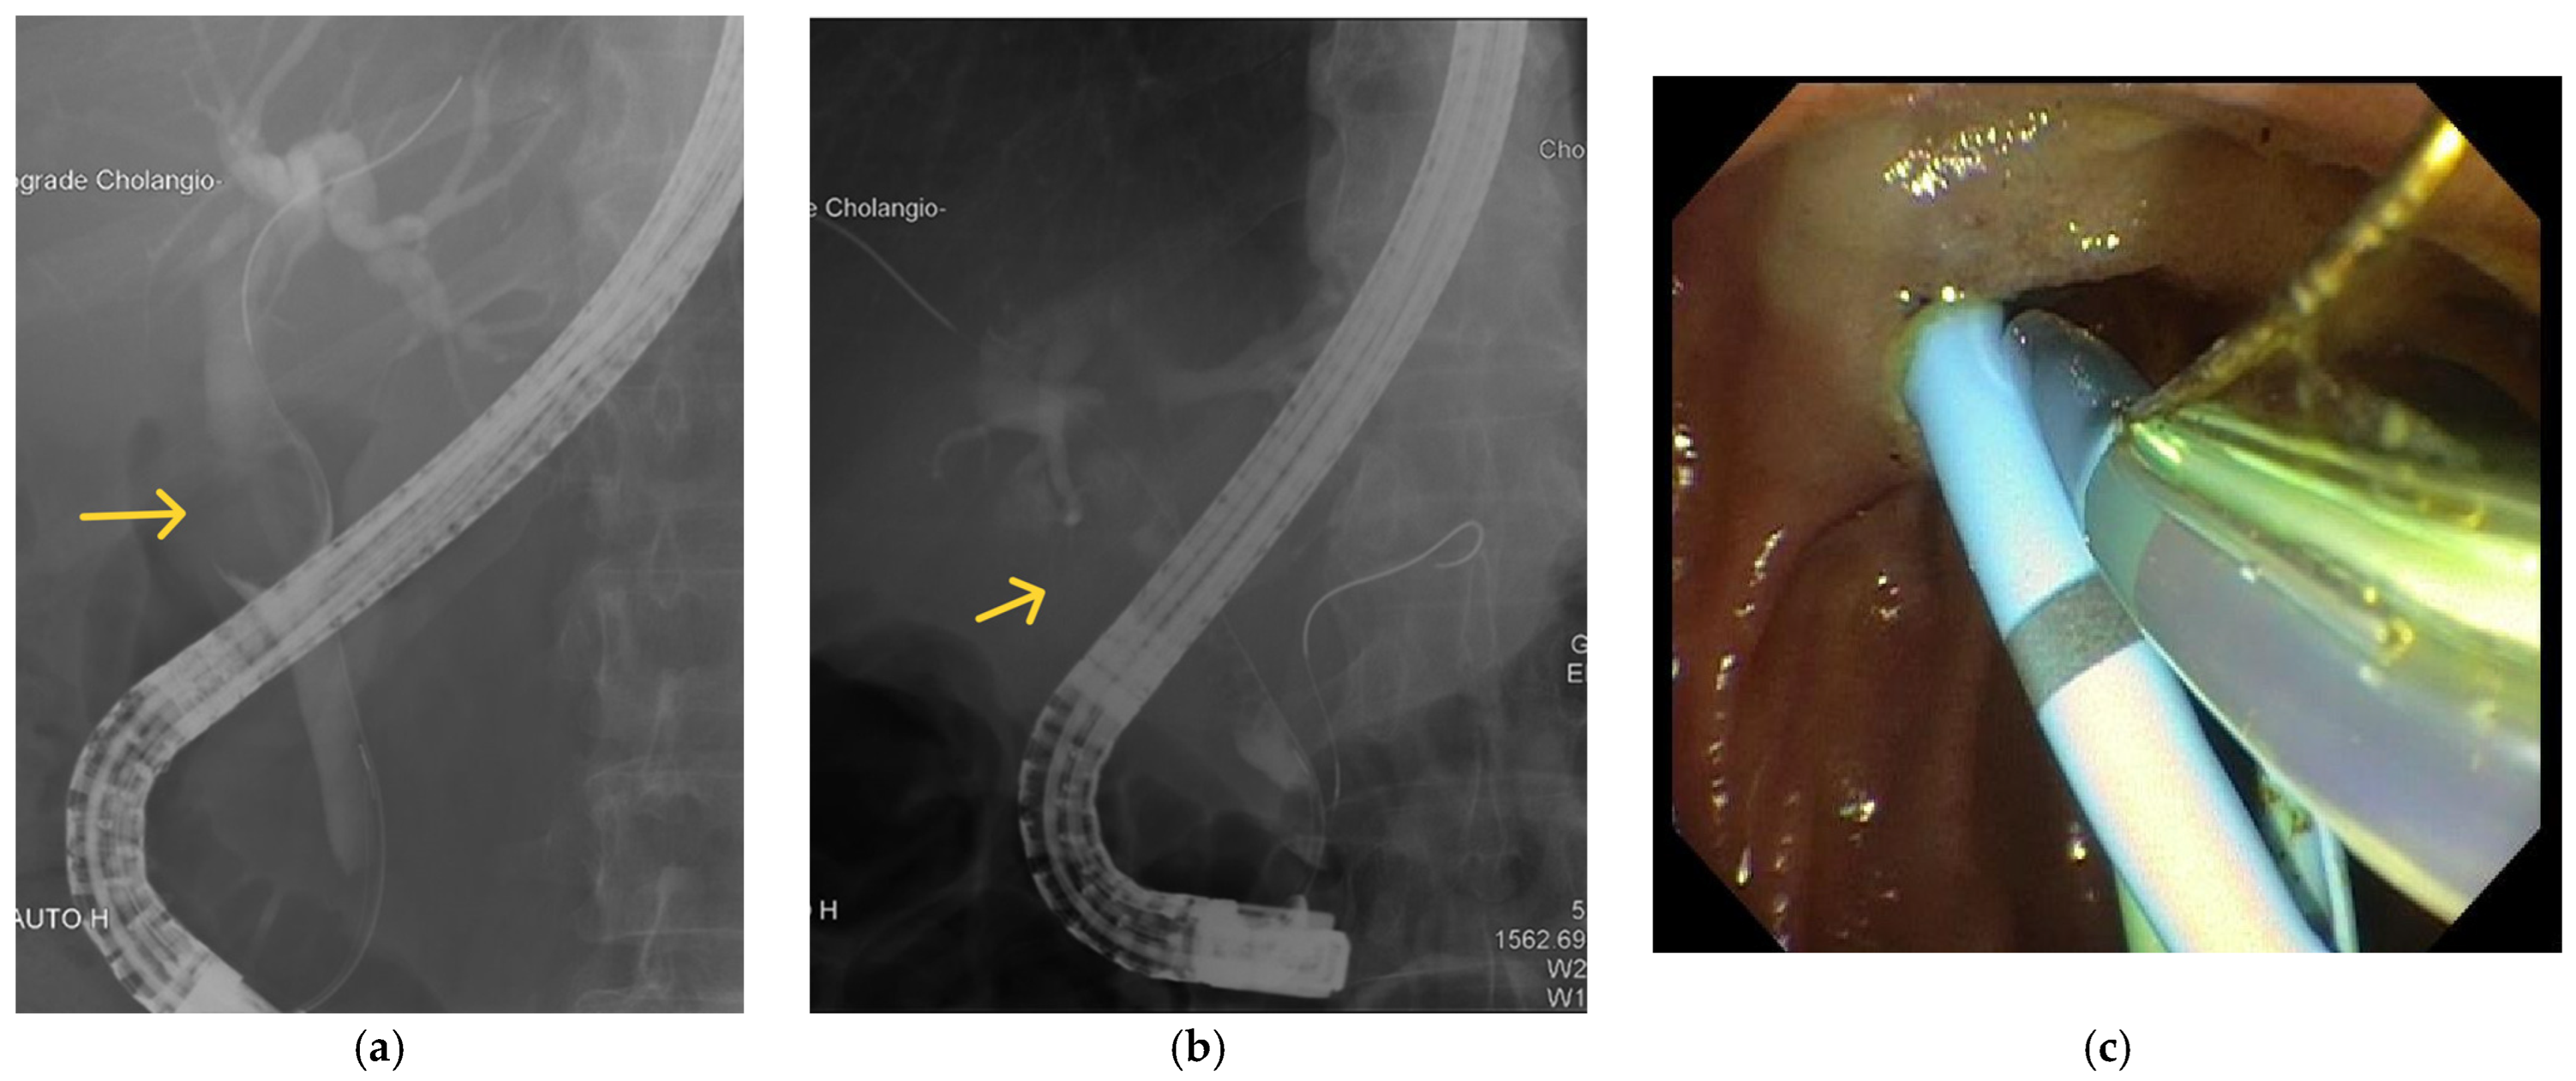

5.4. Endoscopic Retrograde Cholangiopancreatography (ERCP)

6.2. The Role of Endoscopic Interventions